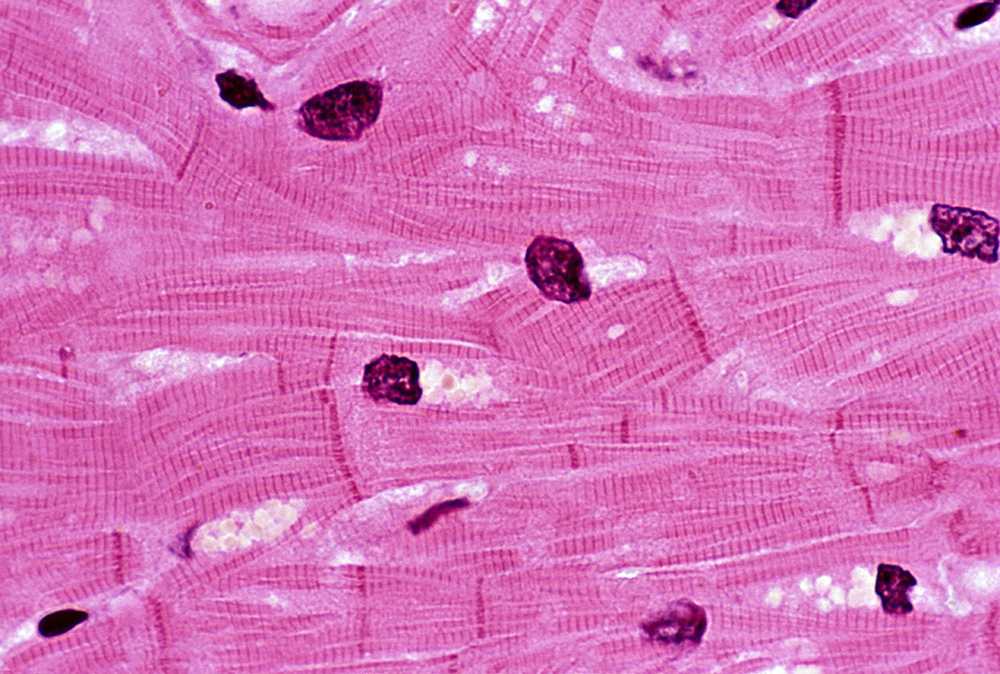

We participated in over 30 clinical trials in 2024, spanning from novel drugs through advanced devices for the treatment of heart failure, valvular heart disease and arrhythmias. Our investigators performed several first-in-human procedures that sought to offer better treatment options for patients with heart disease.